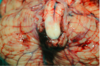

What type of herniation is depicted? Uncal Central (transtentorial) Cingulate (Subfalcine) Transcalvarial Upward cerebellar (transtentorial) Downward cerebellar (Tonsillar)

What type of herniation is depicted? **Uncal** Central (transtentorial) Cingulate (Subfalcine) Transcalvarial Upward cerebellar (transtentorial) Downward cerebellar (Tonsillar)

30

What type of herniation is depicted? **Uncal** Central (transtentorial) Cingulate (Subfalcine) Transcalvarial Upward cerebellar (transtentorial) Downward cerebellar (Tonsillar) Uncal herniation. Arrows point to the medial temporal lobe that has herniated through the tentorial incisura to compress the midbrain